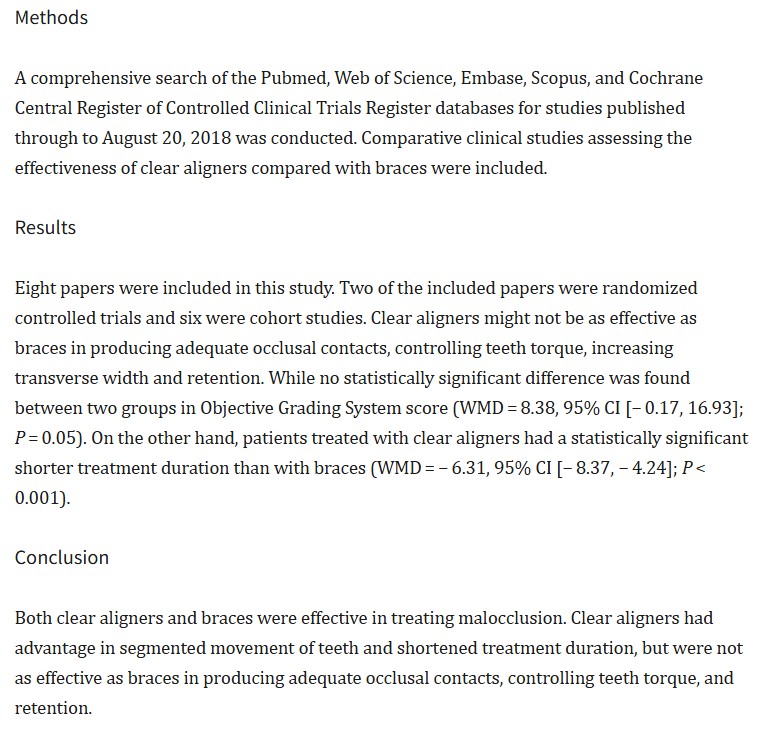

연구 논문 요약

치료 효과, 기간, 편의성 및 만족도 비교

🔹 치료 효과 비교 : 인비절라인은 교합 접촉과 치아 토크 제어에서는 브라켓보다 상대적으로 덜 효과적일 수 있습니다.

🔹 치료 기간과 편의성 : 인비절라인은 구강 위생 관리가 용이하고, 통증이 적은 편입니다. 브라켓은 치료 기간이 더 길 수 있지만, 복잡한 교정에서 더 효율적이고 정밀한 치료가 가능합니다. 또한, 장기적인 사용에 따른 불편함이 있을 수 있습니다.

🔹 환자 만족도 : 인비절라인은 심미성과 통증 감소, 구강 위생 유지 용이성 등에서 높은 환자 만족도를 보입니다.

* 결론 : 인비절라인은 심미성과 구강 위생 관리에 유리하지만, 복잡한 교합 문제에는 브라켓이 더 효과적입니다. 브라켓은 정밀한 교정에 적합하지만 치료 기간이 길고 불편할 수 있습니다. 치료 방법은 치아 상태와 목표에 맞게 선택해야 합니다.

Source : A Comparison of Treatment Effectiveness Between Clear Aligners and Braces최적의 선택을 제시합니다.